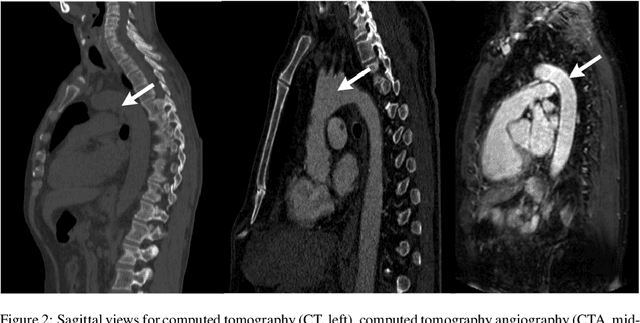

Abstract:The aortic vessel tree is composed of the aorta and its branching arteries, and plays a key role in supplying the whole body with blood. Aortic diseases, like aneurysms or dissections, can lead to an aortic rupture, whose treatment with open surgery is highly risky. Therefore, patients commonly undergo drug treatment under constant monitoring, which requires regular inspections of the vessels through imaging. The standard imaging modality for diagnosis and monitoring is computed tomography (CT), which can provide a detailed picture of the aorta and its branching vessels if combined with a contrast agent, resulting in a CT angiography (CTA). Optimally, the whole aortic vessel tree geometry from consecutive CTAs, are overlaid and compared. This allows to not only detect changes in the aorta, but also more peripheral vessel tree changes, caused by the primary pathology or newly developed. When performed manually, this reconstruction requires slice by slice contouring, which could easily take a whole day for a single aortic vessel tree and, hence, is not feasible in clinical practice. Automatic or semi-automatic vessel tree segmentation algorithms, on the other hand, can complete this task in a fraction of the manual execution time and run in parallel to the clinical routine of the clinicians. In this paper, we systematically review computing techniques for the automatic and semi-automatic segmentation of the aortic vessel tree. The review concludes with an in-depth discussion on how close these state-of-the-art approaches are to an application in clinical practice and how active this research field is, taking into account the number of publications, datasets and challenges.